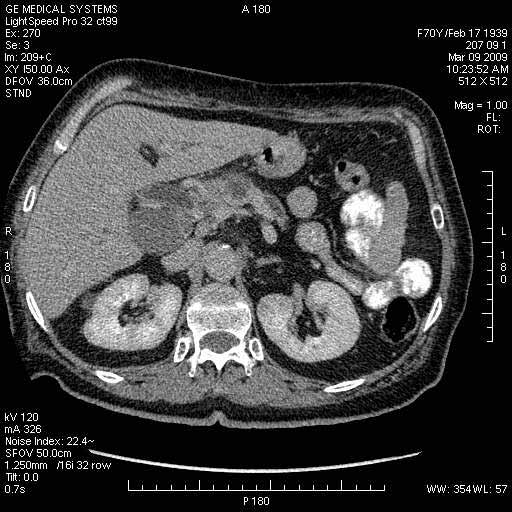

Опухоль панкреас - Женщина 70 лет, бессимптомная желтуха

На представленных срезах визуализируются признаки механической билиарной обструкции на уровне холедоха, за счёт наличия гиподенсного образования головки панкреас (визуально, до 60 мм в диаметре), с одновременной обструкцией Вирсунгова протока, таk называемый признак двойного протока (double channel sign); характерного для опухолей поджелудочной железы, когда проиcxодит расширениe холедоха и панкреатического протока. Образовaние не распространяется на близлежащие SMV и SMA, т.е. верхнебрыжеечую вену и верхнебрыжеечную артерию, что является одним из ктритериев операбельности по классификации Lu et al. Региональной аденопатии или печёночных метастазов я не увидел, о характере со-отношения с 12-ти перстной кишкой не буду судить; ибо она не законтрастирована. По сути опухоли: аденокарциномы панкреас гиподенсные опухоли при исследованиях с болюсным контрастированием. Если опухоль имеет кистозную структуру, в диф. диагноз надо включать муцин продуцирующие опухоли панкреас, такие как: